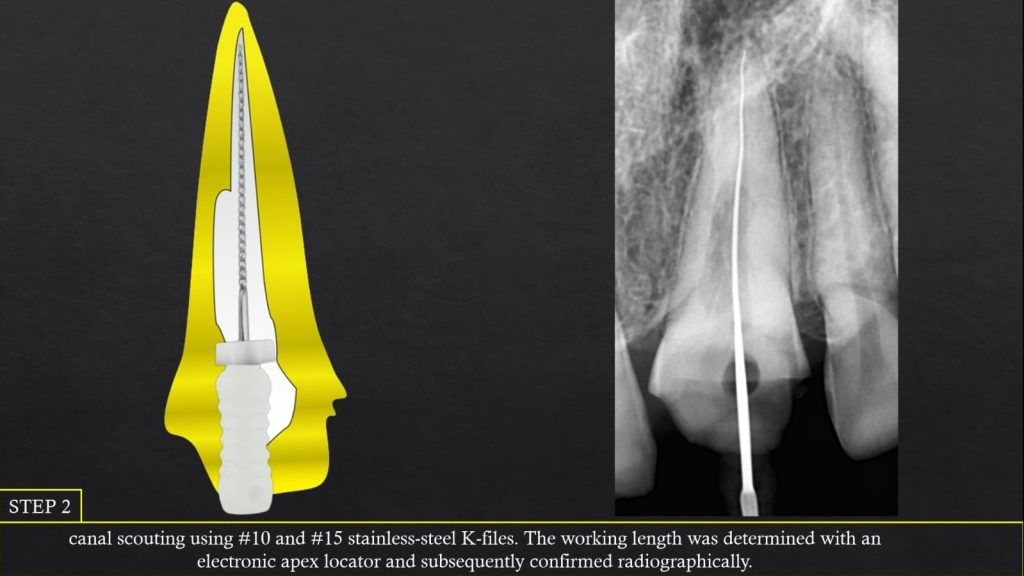

Clinically , IRR may go unnoticed until detected radiographically. However traditional radiographs can miss early lesions, whereas CBCT offers precise three-dimensional evaluation, especially in complex or perforated cases. Histologically, resorptive areas may show granulation tissue or bone-like deposits depending on the type. Management focuses on eliminating the pulp tissue and sealing the resorptive defect using advanced techniques such as warm gutta-percha, bioceramic sealers , or regenerative protocols when perforation is present.